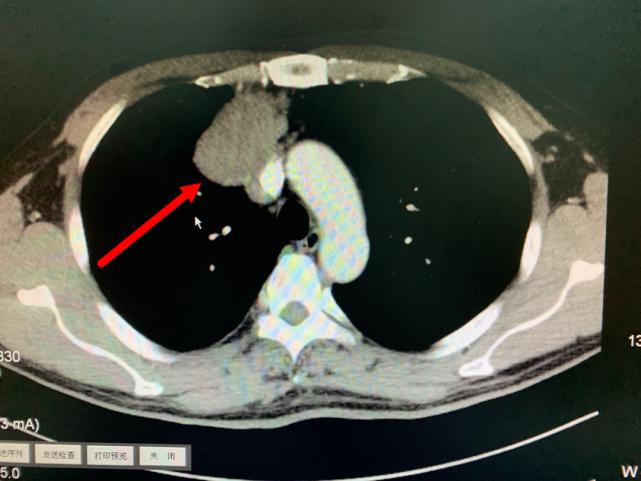

今年11月份,老方因“肠炎”在浙江省立同德医院肛肠科住院。“新冠”期间住院需要常规做胸部CT筛查,检查出来的结果却让他和医生们大吃一惊,胸部CT显示:胸腔内存在一个巨大肿瘤即纵膈肿瘤,大小约10.0cm×6.5cm×7.0cm,大小和一个成人男性拳头差不多。肿瘤紧靠着肺部、心脏及大血管,且与部分大血管有粘连,对重要的脏器已经造成了挤压。在确定胃肠道没有严重病患后,老方被转入心胸外科进一步作检查、治疗。

箭头所指为巨大纵隔肿瘤

叶中瑞主任医师通过进一步增强CT检查发现,老方体内的肿瘤巨大、与相邻的重要脏器粘连,界限不清,手术难度较大,且微创手术不适合,于是采取正中劈开胸骨的手术方式。手术过程顺利,术后恢复良好。第二天即下床活动。术后病理结果显示:纵膈肿瘤性质为中度恶性的胸腺肿瘤,后续还需要做进一步的放射治疗,以防止复发。老方在庆辛之余,他告诉叶中瑞主任医师,自己从今年开始每年都按时做体检,争取做到疾病早发现、早治疗,避免错过疾病的最佳治疗时机。